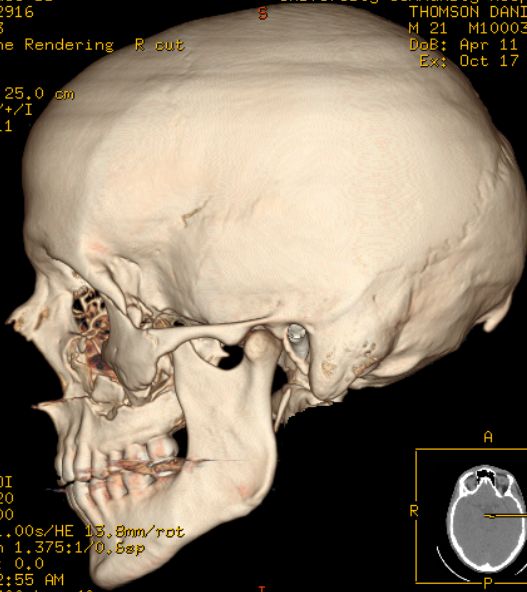

| Danny Thomson estava jogando beisebol com o irmão menor quando de repente este acertou a bola em cheio que veio, a mais de 160 por hora, em direção ao seu rosto. A bolinha acertou sua bochecha esquerda e fez um tamanho de um estrago que precisou de cirurgia para ser reparado. Vejas as imagens: |

dois olhos roxos eu não sei, mas a 4° foto eh o rabisco q os medicos fazem antes da cirurgia, pra sabe aonde eh q tem q mexe e tals...

a bola rachou o cranio dele, ou eu que vi a tomografia zuada?????

Tomografia 3D show de bola !!!!